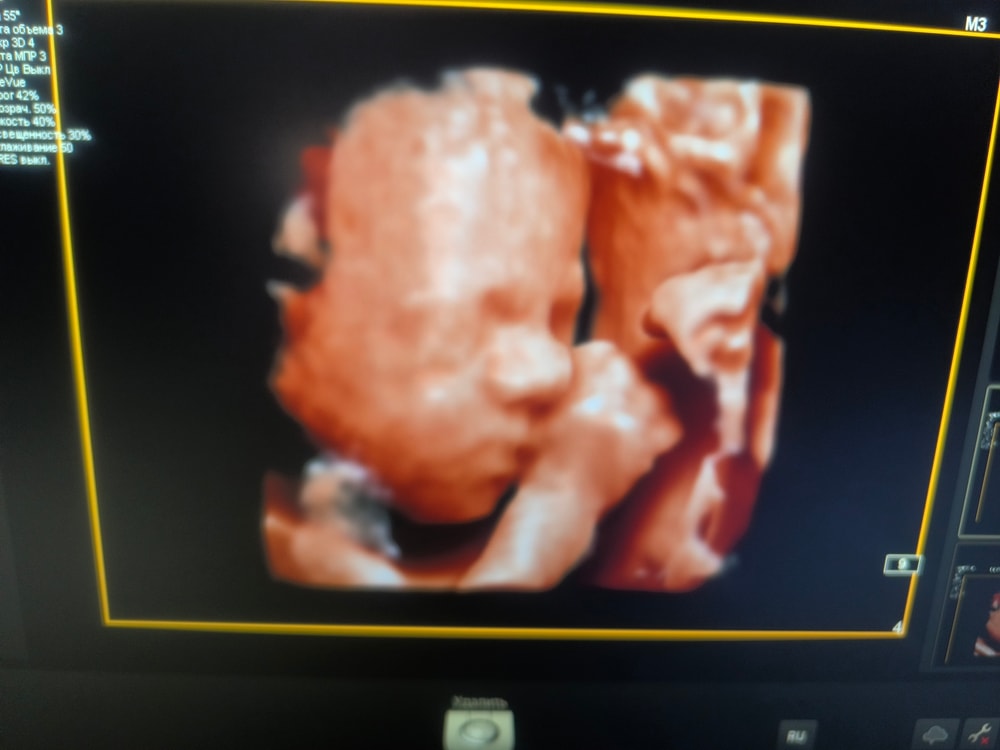

Узи 27и6 недель

Съездили сегодня на узи в Днк клиник по рекомендации девушки к Горяиновой . Оооочень понравилась, теперь она мой топчик. 😍

Бусинка наша 1097 гр. Все развито по срокам, все в норме 🙏Волос сказали мало пока, только только пушок вылез, но возможно вырастут еще, у старших детей длиннющие шевелюры были.

Так интересно наблюдать как дети там существуют ... Чудо техники все же 😀